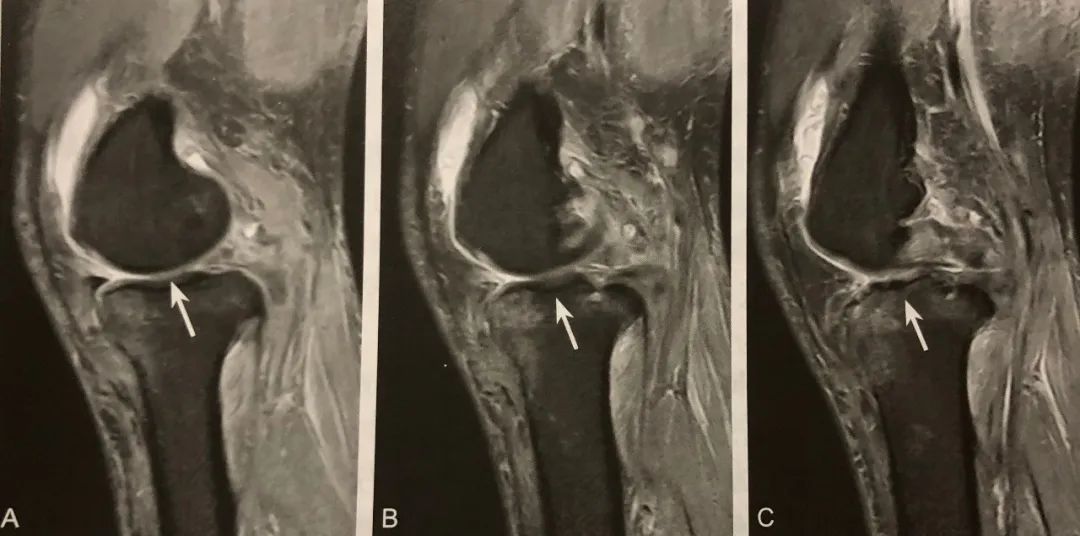

阅片要点:

1. ACL黏液样变性的特征性征象;

2. 在膝关节 MRI 矢状位观察;

3. 芹菜杆征对于诊断 ACL 黏液样变有较高的特异性和敏感性;

4. 注意与 ACL 撕裂鉴别。